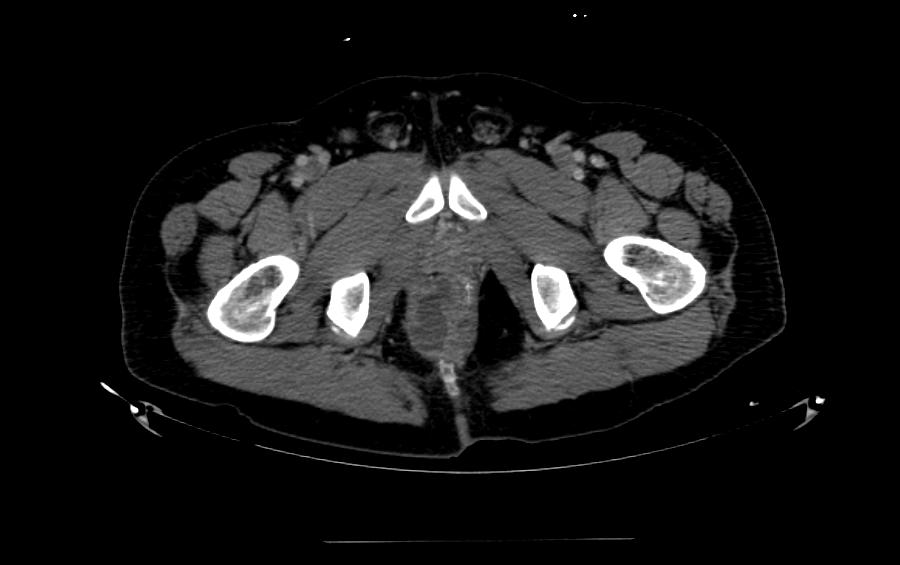

CT検査

CT検査は、膿瘍の範囲や周囲の組織への広がりを確認するのに有用です。特に、深部膿瘍や広範囲の感染が疑われる場合に行われます。ただし、MRIと比較すると軟部組織の描出はやや劣ります。

肛門周囲膿瘍のCT検査イメージ:膿瘍の範囲や深さを確認します。